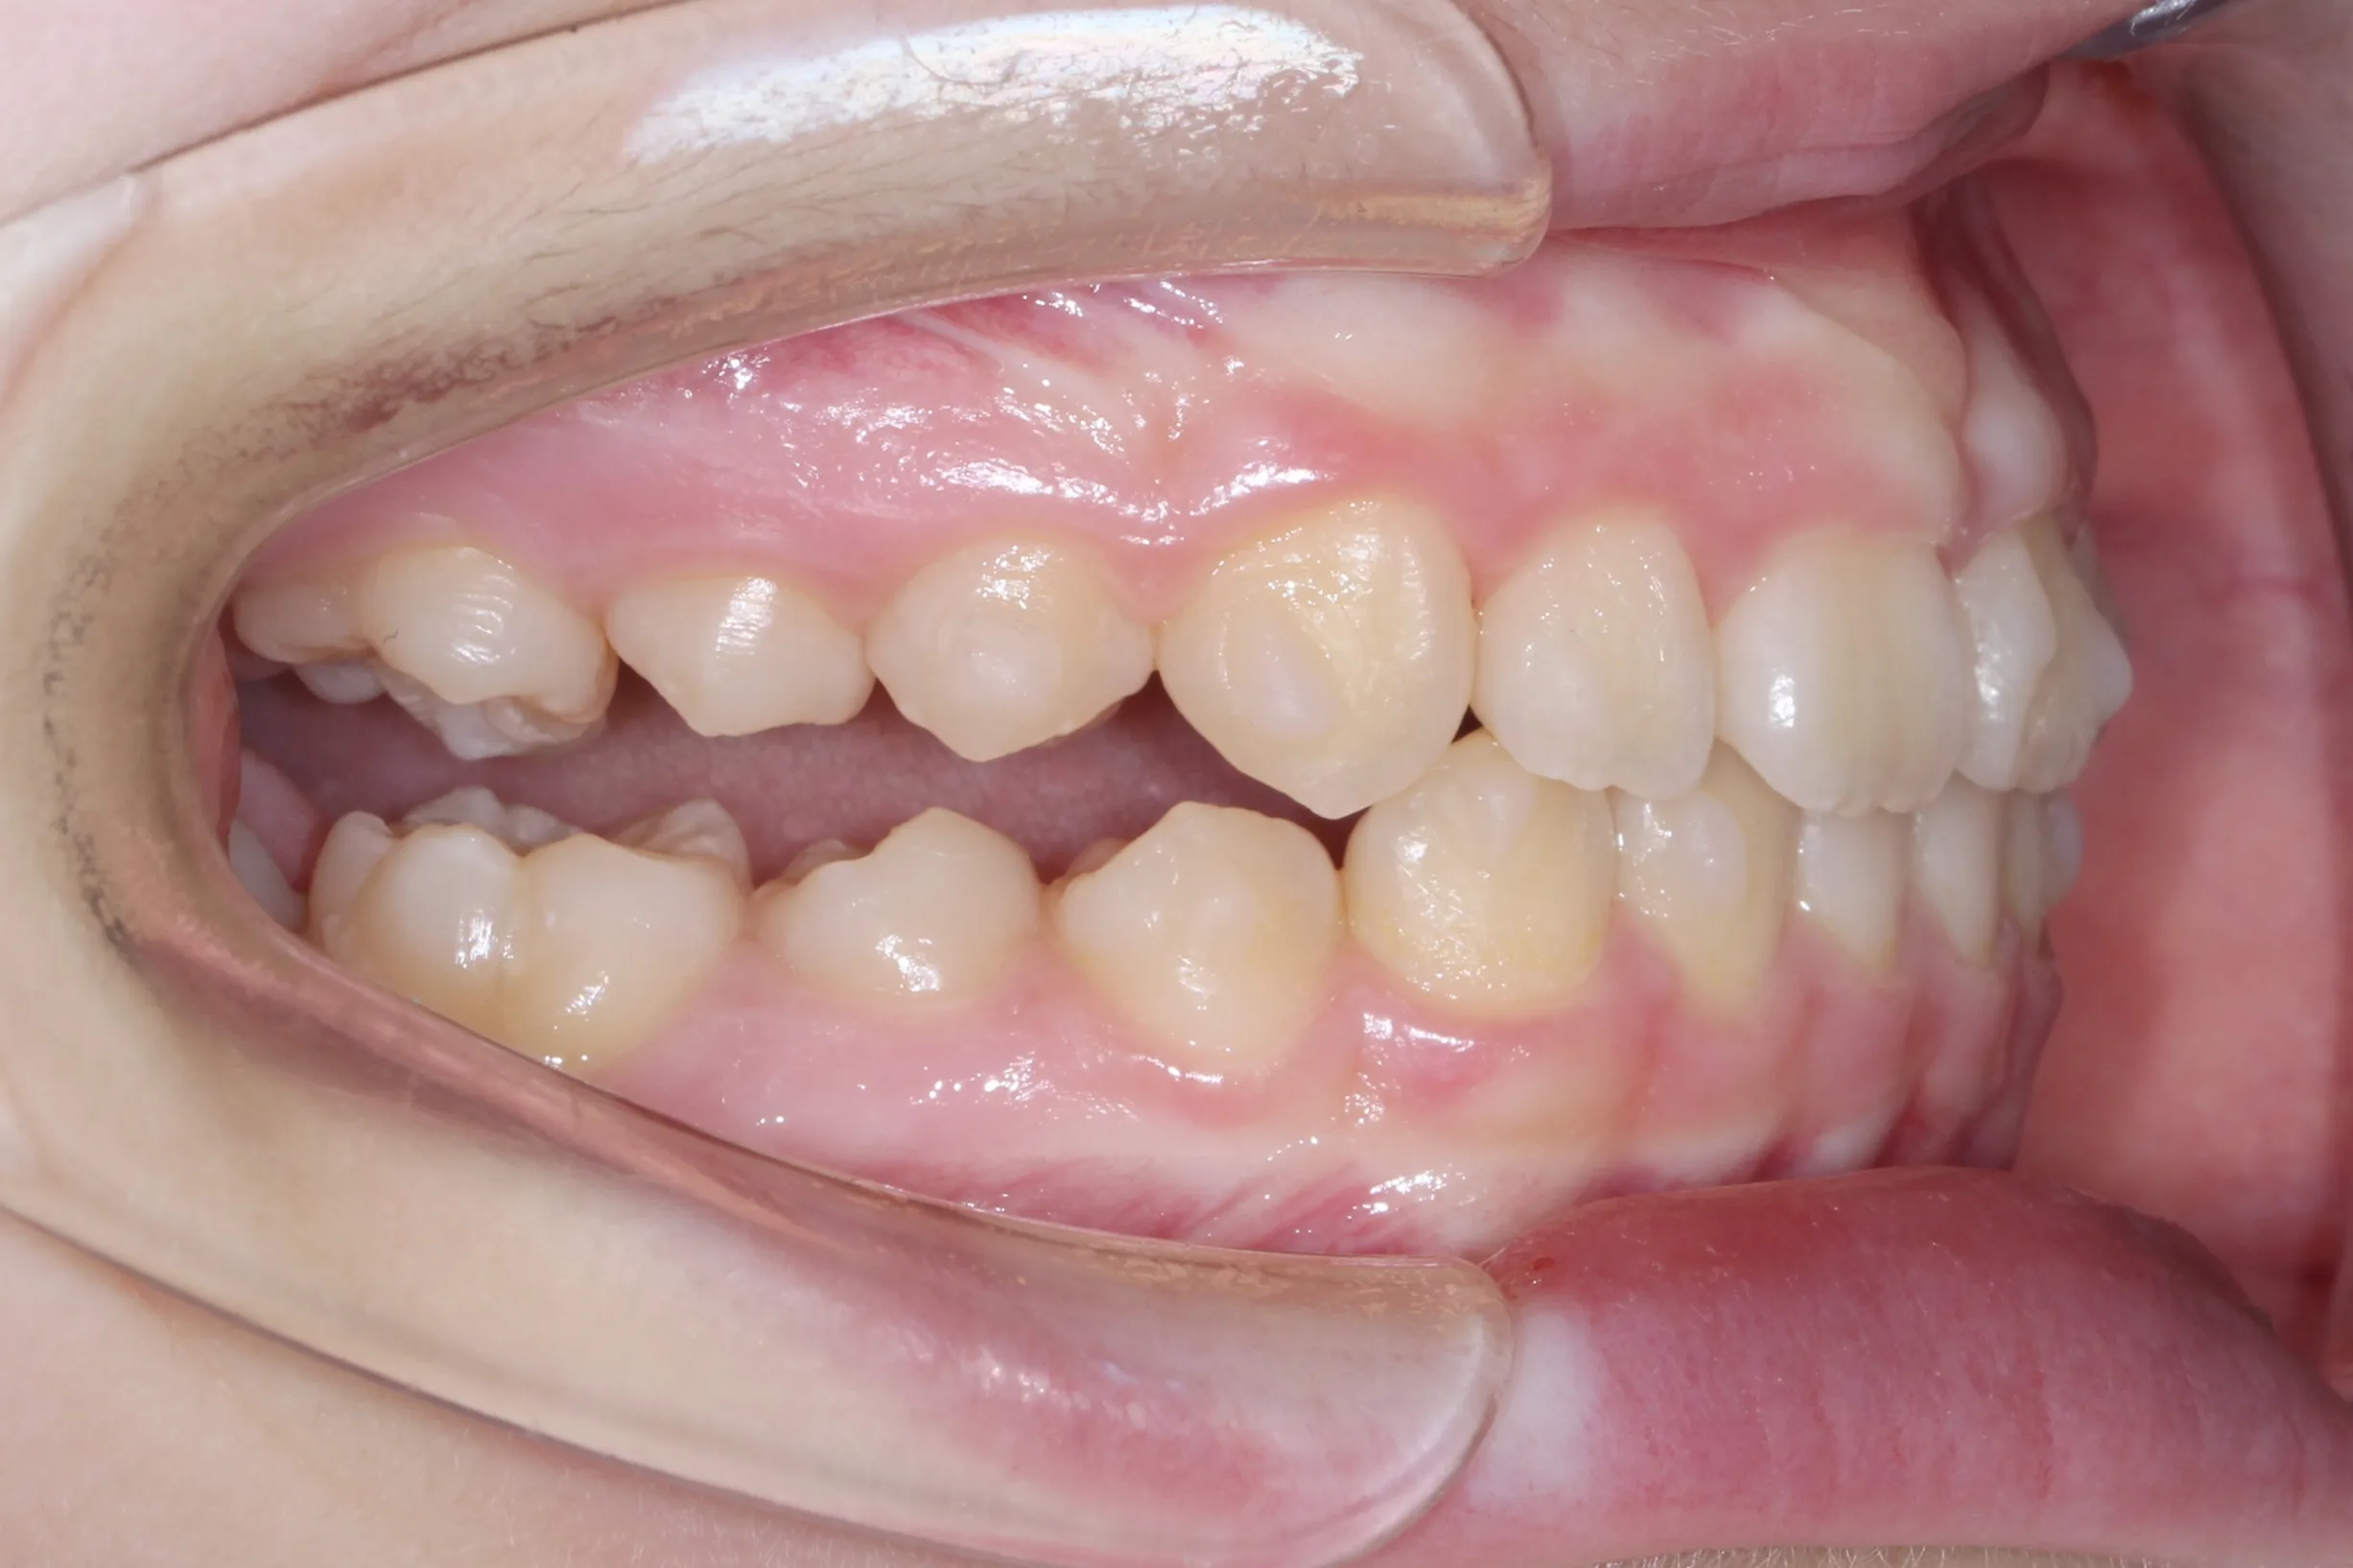

만 11세 환자분께서 튀어나온 앞니와 다물어지지 않는 입술 때문에 내원하셨습니다. 검진 결과 상악 전돌을 동반한 2급 부정교합(Class II malocclusion) 상태였으며, 아래턱의 성장이 다소 부족하여 골격적인 조화가 필요한 상황이었습니다.

이번 치료에는 인비절라인 퍼스트(Invisalign First)에 하악 전방 견인(Mandibular Advancement, MA wing)을 추가하여 치료를 진행하였습니다. 성장기라는 시기적 특성을 적극 활용하여 아래턱의 점진적인 성장을 유도하고, 과도한 상악 전치부 돌출을 개선하는 데 치료의 핵심 전략을 두었습니다.

2년 7개월의 치료 과정을 거치며 환자분의 협조도 덕분에 안모 프로파일과 교합이 안정적으로 개선되었습니다. 성장기라고 해서 무조건 교정이 어려운 것은 아닙니다. 적절한 시기에 맞춤형 장치를 선택한다면 골격적 불균형을 효과적으로 바로잡을 수 있습니다.